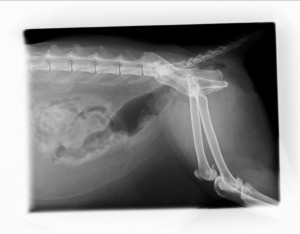

切除した巨大結腸&カチカチの便 切除後の大腸を吻合、短くなりました。